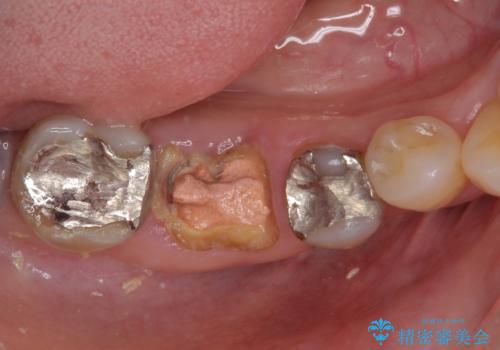

![[ 欠損補綴 ] ブリッジとインプラントの症例 治療前](https://seimitsushinbi.jp/wp/wp-content/uploads/2021/10/d680d397e015686572db595995781e12-500x350.jpg?v=1634192539)

![[ 歯牙破折 ] 違和感のある大臼歯 ブリッジ治療の症例 治療前](https://seimitsushinbi.jp/wp/wp-content/uploads/2021/08/IMG_9577-500x350.jpg?v=1629711075)